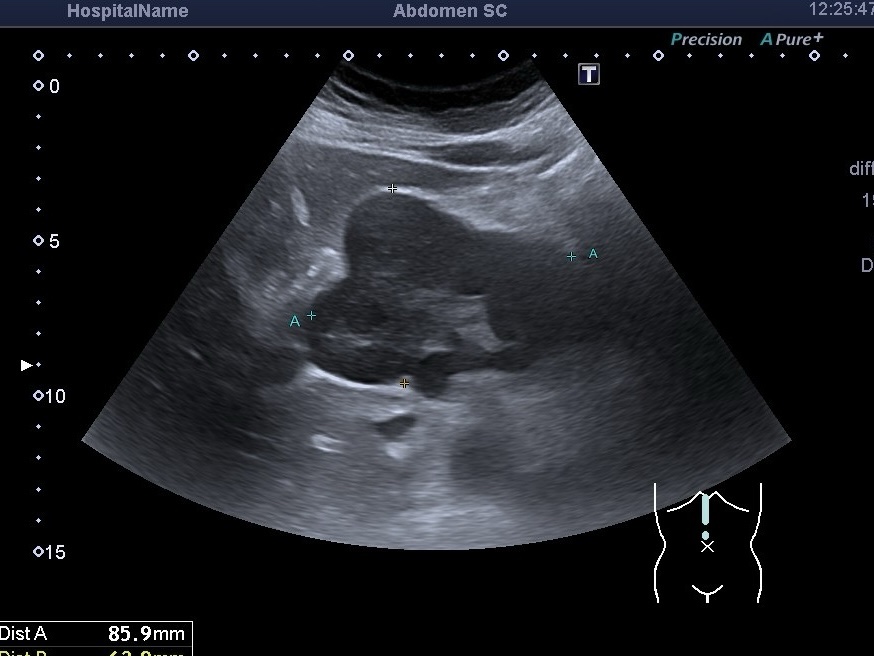

УЗД органів черевної порожнини при захворюваннях крові Під час ультразвукового дослідження (УЗД) органів черевної порожнини увагу звертають не лише на...